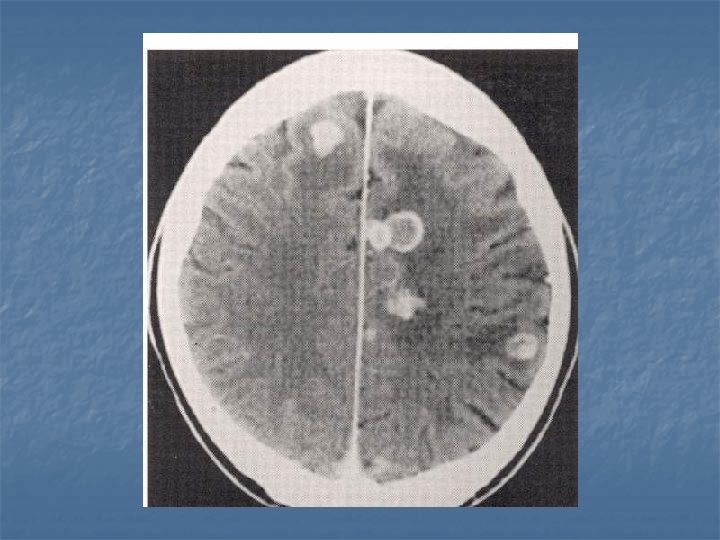

Toxoplasmosis n n n Yer kaplayan lezyonların % 60’ı % 30 olguda mevcut Kortikomedüller bileşke (? ), basal ganglion ve talamusda sık tutulum BT-MR. . . >5 lezyon, halka tarzında kontrast (+), nodüler, ödem ve kitle etkisi Erken tanı önemli. . . tedavi edilebilir 2 hafta primethamine+sulfadiazine